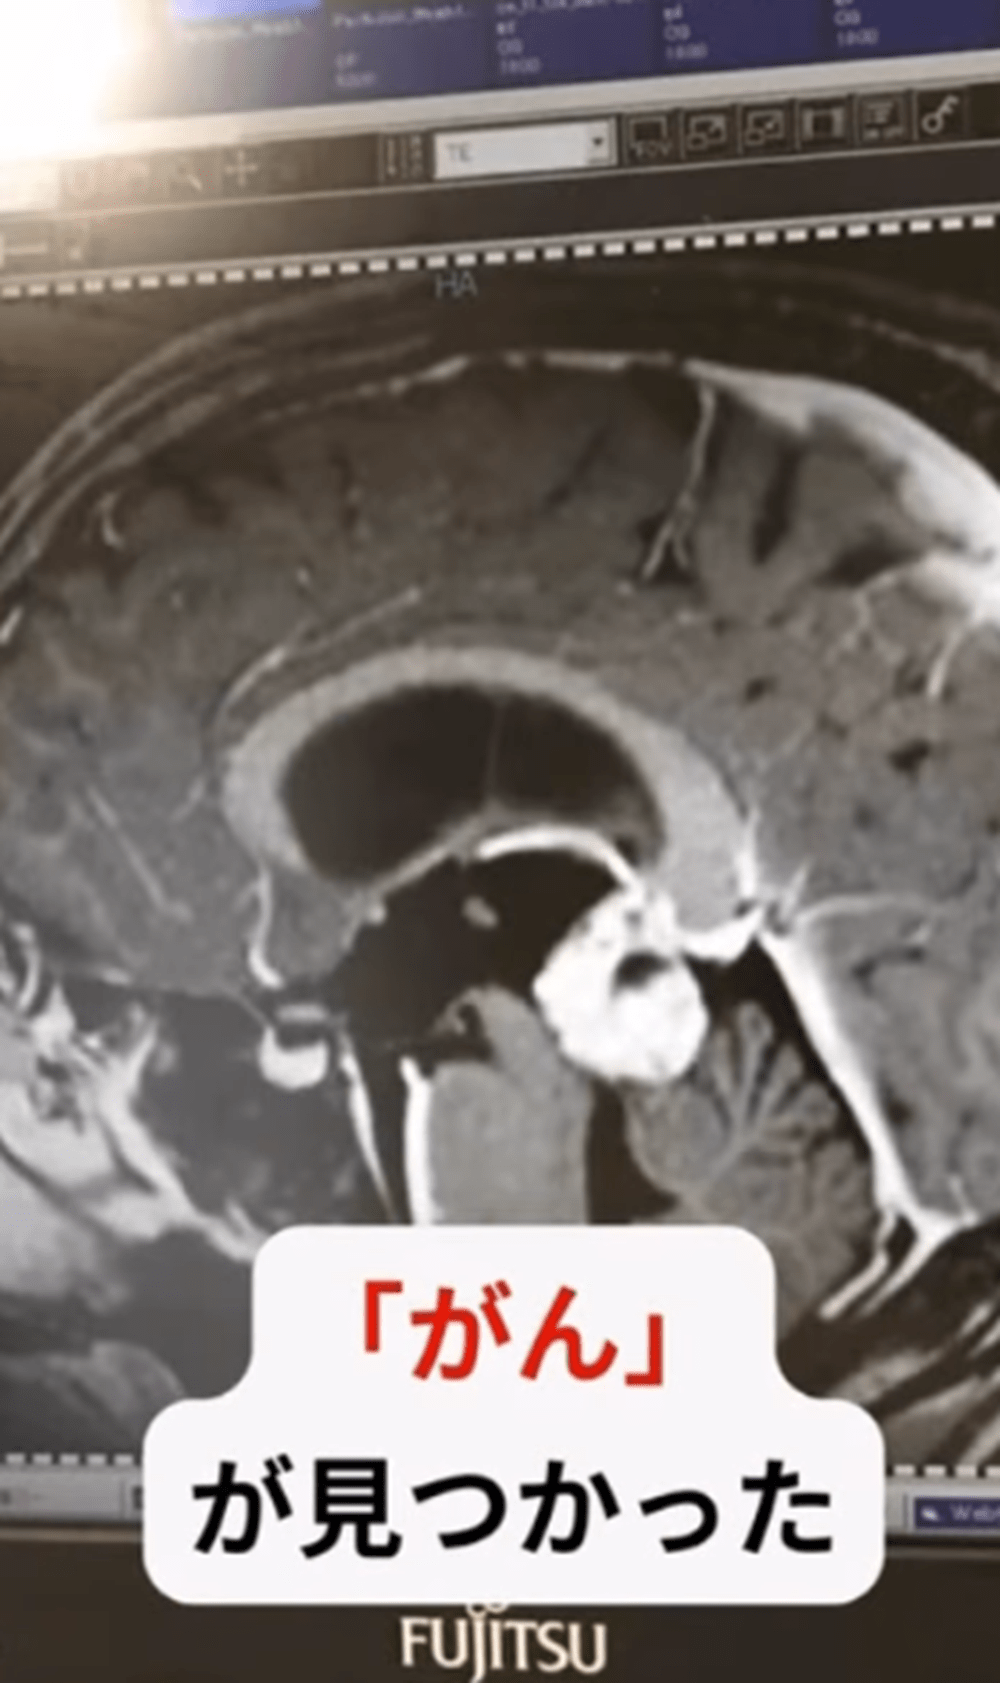

突如、倦怠感と吐き気に襲われ…緊急手術の末に判明した病 目標が繋いだ生きたいと願う思いに迫る

• 女性「なんの自覚症状もなかった」健康診断で検査した結果…→医者「腫瘍があります」手術になった女性の体験に「大変」の声